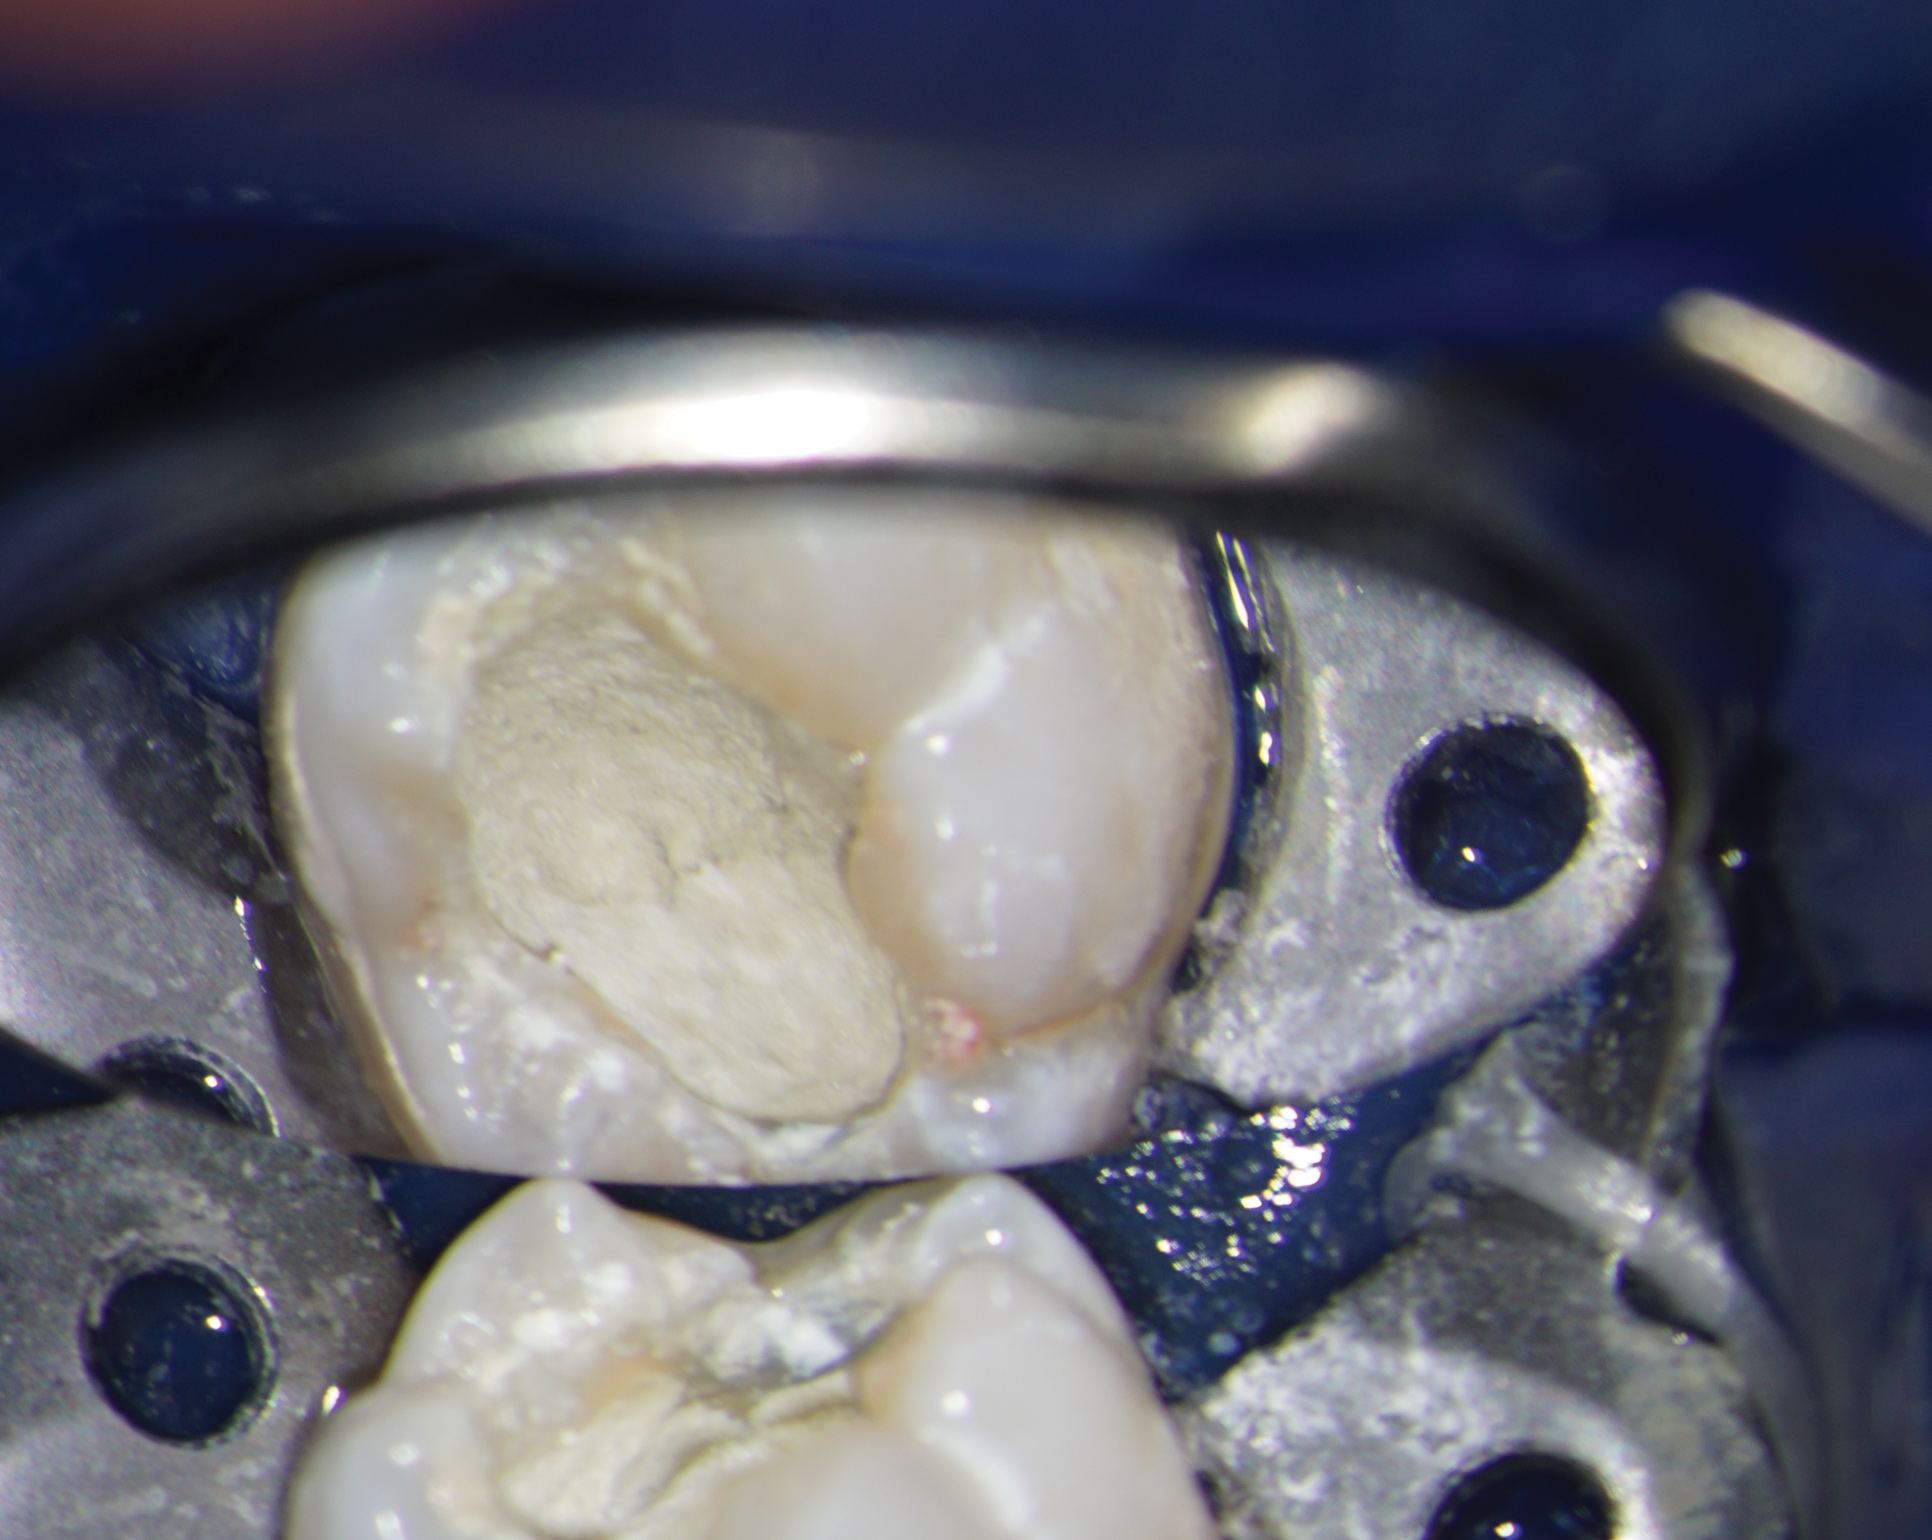

Obtaining a pretreatment pulpal and periradicular diagnosis before performing restorative treatment helps the clinician better understand how to treat the dental pulp, especially if it is exposed during caries excavation (Figure 1). A recent study by Ricucci et al found that a clinical pulpal diagnosis of a normal pulp or reversible pulpitis had a 96.6% histological match to the actual pulp tissue in a tooth.17 Therefore, for patients who present with or without pain from a carious pulp exposure and a pulp diagnosis of a normal pulp or reversible pulpitis, the tooth can be successfully treated with a mineral trioxide aggregate (MTA) pulp capping or pulpotomy if the pulp is exposed during treatment.18 In a randomized clinical trial, Hilton et al reported that MTA performed significantly better than calcium hydroxide as a direct pulp-capping agent.19

Fig 1. Obtaining a pretreatment pulpal and periradicular diagnosis prior to restorative treatment allows the clinician to properly treat the dental pulp if exposed during caries removal. Here, radiographic evidence of decay is shown on tooth No. 29 (arrow).

Figure 1